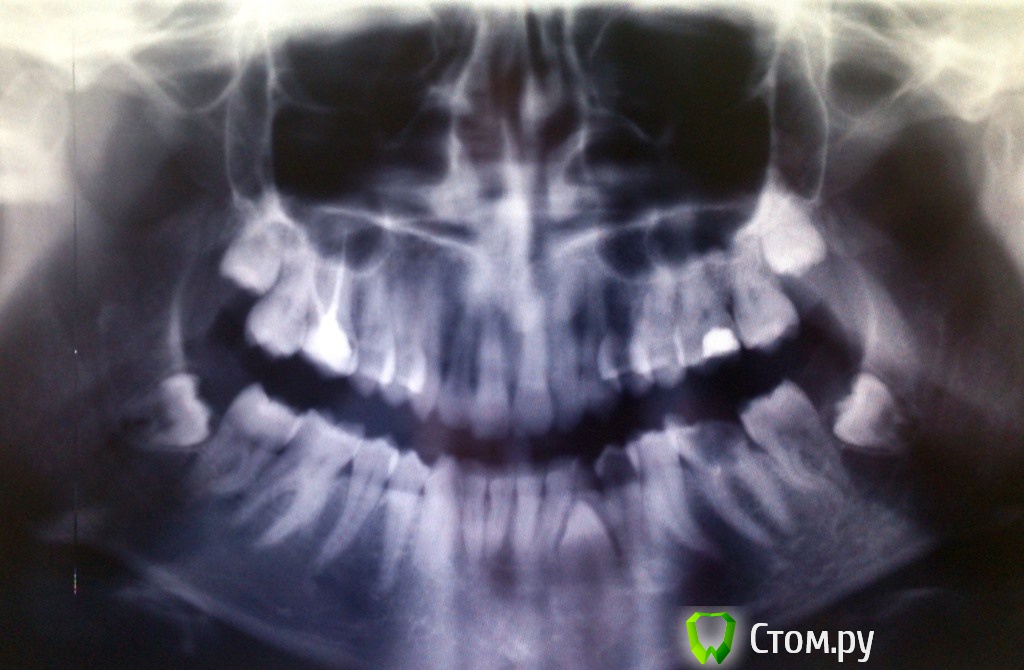

sunbeam Опубликовано 29 июня, 2014 Автор Поделиться Опубликовано 29 июня, 2014 Прикрепила панорамный снимок Ссылка на комментарий

red_butler Опубликовано 29 июня, 2014 Поделиться Опубликовано 29 июня, 2014 Снимок плохого качества, но и по нему видно, что нужно удалять зубы мудрости, срочно лечить 3.6 зуб. И искать толкового ортодонта Ссылка на комментарий